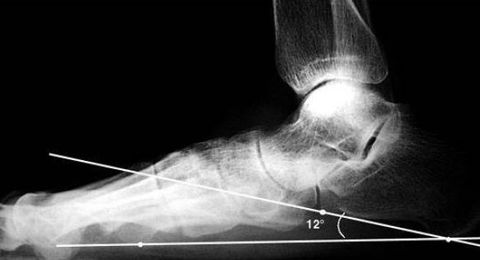

| What is this angle called? What foot type does it indicate? | Talar - 1st MT or Meary's Angle Pes plano-valgus |

| What is this angle called? What foot type does it indicate | Talar - 1st MT or Meary's Angle Pes cavo-varus |